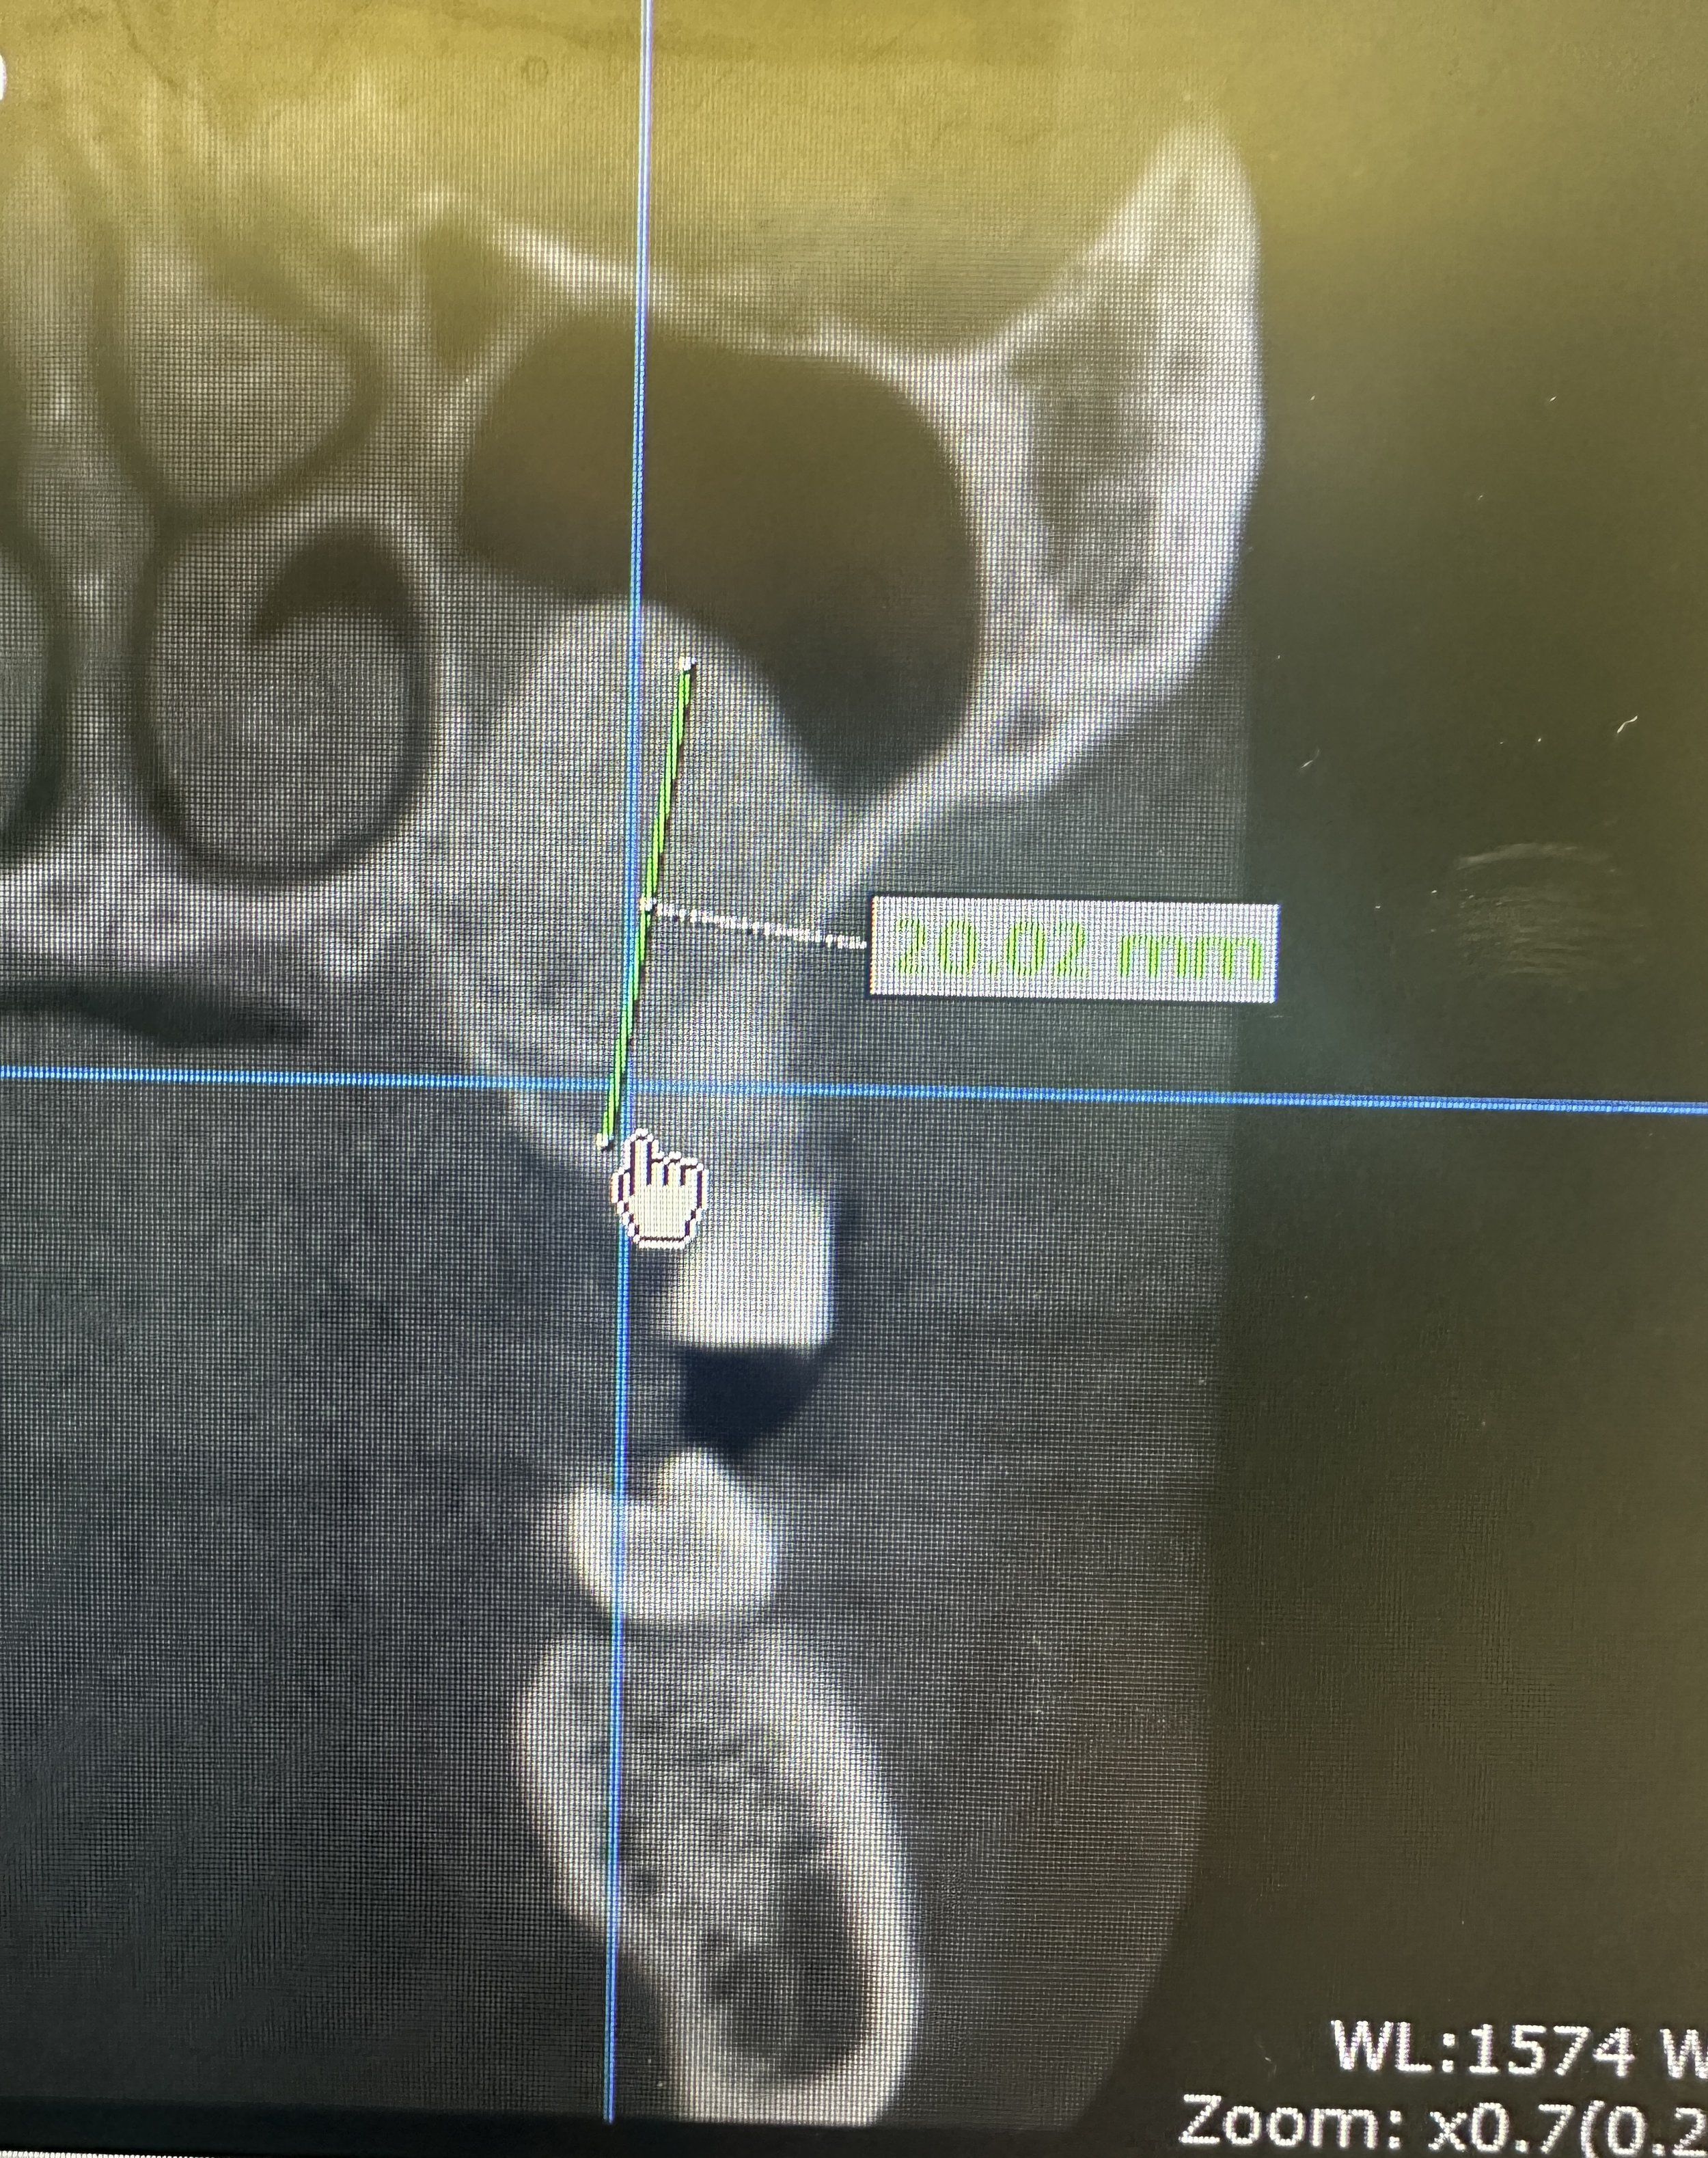

In this case, the patient presented with reduced vertical bone height in the upper left posterior region, making implant placement at site #14 unsuitable without prior augmentation. Advanced imaging confirmed the proximity of the maxillary sinus and the need for a staged surgical approach.

To restore the foundation for implant placement, a left maxillary lateral window sinus lift was performed. This technique allowed for controlled elevation of the sinus membrane and precise placement of bone graft material, increasing available bone volume while preserving surrounding anatomy.

Following adequate healing and bone maturation, implant placement at site #14 was completed with improved structural support and optimal positioning. Post-operative imaging demonstrated successful bone regeneration and stable integration of the implant within the augmented site.